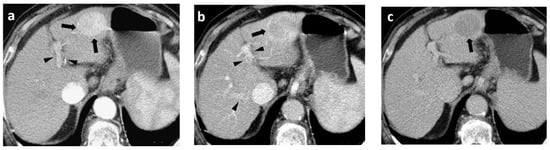

The typical imaging hallmark diagnostic feature of HCC is the combination of non-rim arterial hyperenhancement (non-rim APHE) on the late arterial phase and non-peripheral wash-out appearance on the portal-venous and/or delayed phases on MDCT or MRI, thereby reflecting the peculiar vascular derangements that occur during hepatocarcinogenesis [

Figure 5). According to the latest EASL/EORTC (European Association for the Study of the Liver/European Organization for Research and Treatment of Cancer) guidelines issued in 2018, a definite diagnosis of HCC can be established in a nodule measuring ≥10 mm or based on a background of liver cirrhosis or other risk factors for HCC, if these typical imaging hallmark features are encountered [

Figure 5. Typical hallmark imaging features of HCC in a 60-year-old patient with HBV cirrhosis. (a) Late arterial phase, (b) Portal-venous phase, and (c) Delayed phase. MDCT images show a 30-mm mass in the left liver lobe with global APHE (arrows) (a) “wash-out” on the PVP (arrow) (b), and capsule appearance on both the PVP and delayed phase (arrow) (b,c). Note the enhancement of both the left hepatic artery and portal vein with no enhancement of the hepatic veins on the late arterial phase (arrowheads) (a) and enhancement of the left hepatic artery, portal vein, and hepatic veins on PVP (arrowheads) (b).